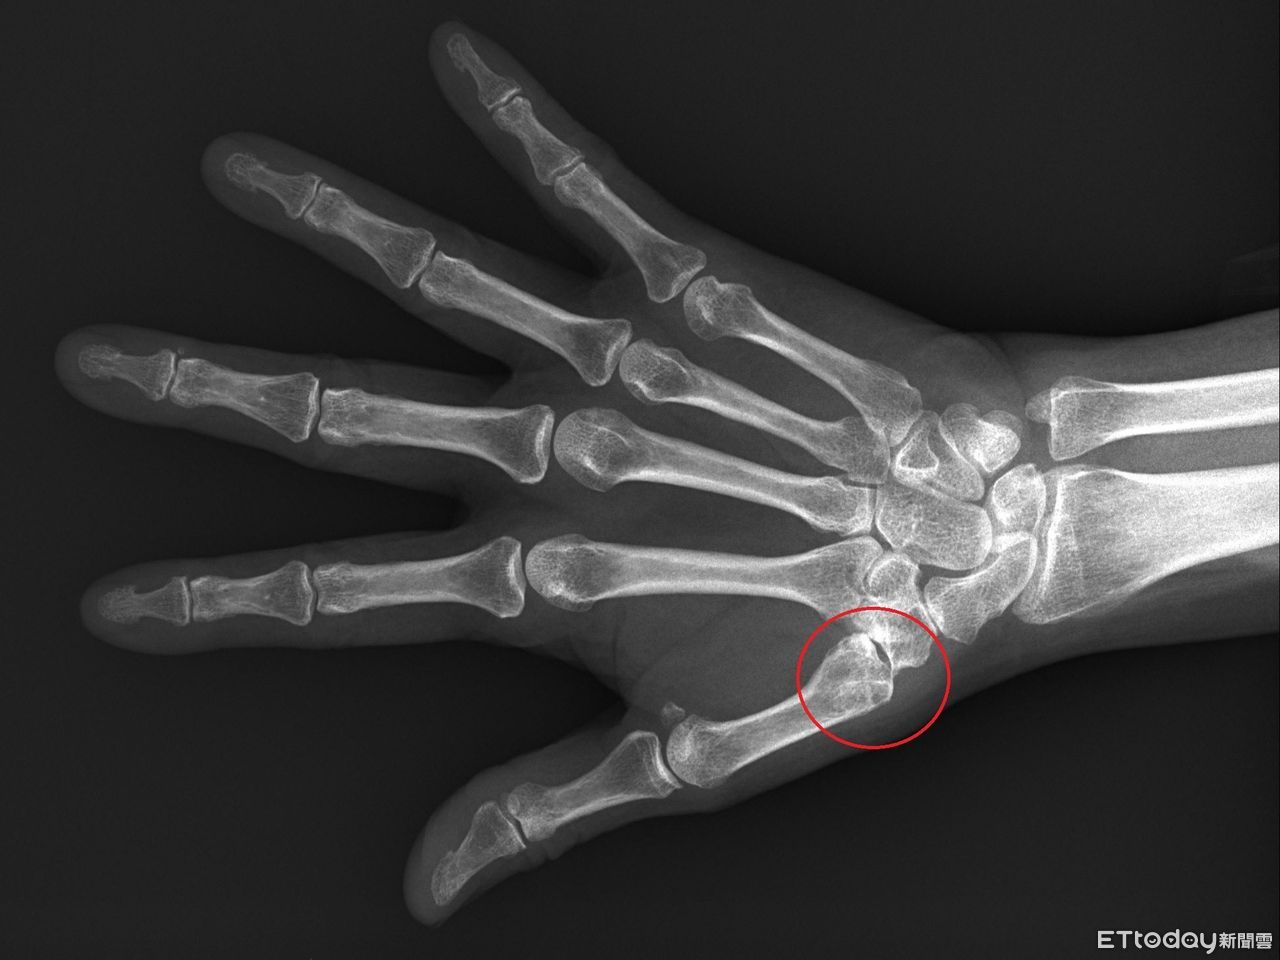

▲拇指無力要當心是否關節已鬆脫。(圖/台北慈濟醫院提供)

周博智說明,臨床會以X光判斷關節磨損程度,若程度尚輕,可以用貼紮或護腕固定,加上止痛藥物控制,但在這樣的保守治療下仍然影響生活工作機能,另現在也有新式微創手術進行治療,先在手腕開0.5~1公分的入口,再將滑脫關節矯正至關節軸心,而後將可吸收的螺釘固定在第二掌骨基部,以第二掌骨基部借力使力,就可以分攤拇指基部的受力,而且不會犧牲拇指的靈活度。